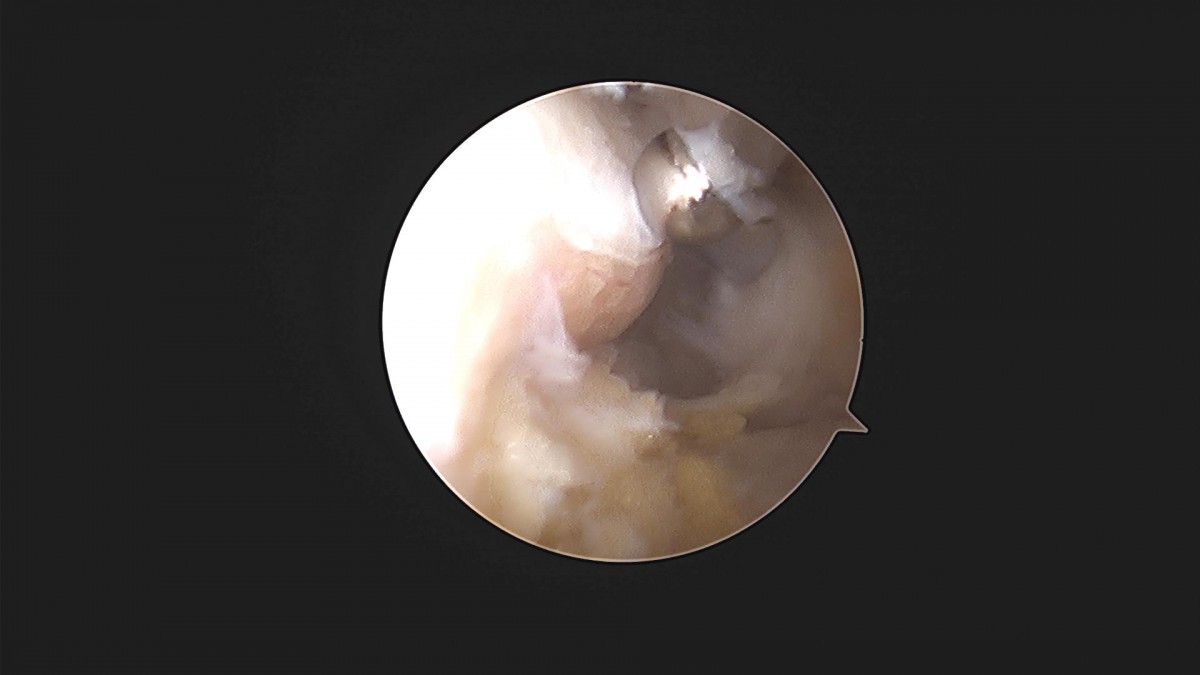

이재상원장님 발목 인대봉합술(3187)조용O 환자

작성자 최고관리자 댓글 0건 조회 1,408회 작성일 22-04-12 17:47